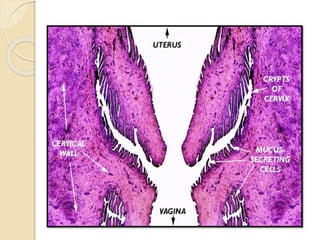

Cervix (Neck of uterus):

 Thick walled, muscular tube rich in elastic fibers.

 The mucosa-submucosa forms high primary, secondary and

tertiary folds. The lining epithelium is simple columnar with

many mucigenous cells including goblet cells.

 Lamina propria-submucosa contains dense irregular

connective tissue with collagenous and elastic fibers. Intra-

epithelial and simple tubular glands are present in ruminants.

Uterine glands do not extend into the cervix.

 Tunica muscularis consists of Inner circular and outer

longitudinal muscle layers. Elastic fibers are prominent in the

circular layer.

 Tunica serosa contains loose connective tissue covered by

mesothelium.

Vagina:

 Muscular tube with flat longitudinal mucosal-

submucosal folds throughout the its length.

 It is lined by stratified squamous non-cornified